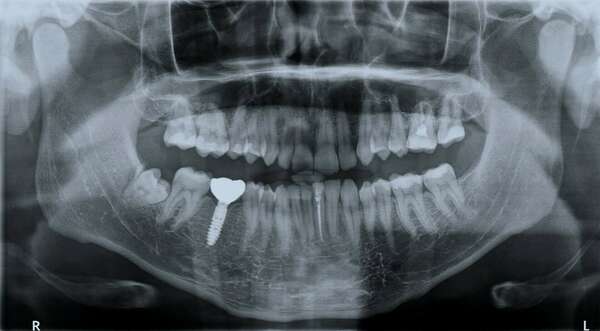

La mise en place des implants peut paraître impressionnante. Il s’agit pourtant d’une intervention assez rapide dont les suites se passent généralement bien.

Votre chirurgien-dentiste a identifié dans votre bouche une ou plusieurs dents absentes. Ces édentations sont la conséquence de déchaussements, de fractures ou d'infections. Dans tous les cas, il est impératif de les remplacer.